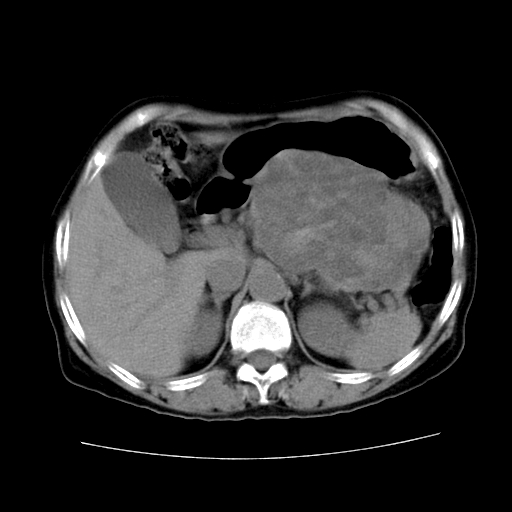

女性,72岁。

主诉中上腹部疼痛不适1年余。

胰腺尾部不规则巨大略低密度肿块,界限清楚,内密度不均,增强动脉期不均匀强化,门脉期明显退减并低于胰腺密度,肿瘤包埋于脾血管。多考虑;来源于胰腺尾部的“胰腺癌”。

1、这个病例确实有点难。影像主要显示胰腺体尾部占位,我们当初也是诊断胰体尾部囊腺癌可能性大,而且读片会上也很多人这么诊断的。

2、手术所见:打开腹腔发现胃与胰腺体尾部可见肿块,大小约10×8×11cm,质硬,不可推动,周围血供丰富。术中诊断:胃肿瘤侵及胰腺体尾部。

1)、胃小弯侧胃肠间质瘤(考虑恶性),瘤体大小13.5×7×6.5cm,上下切缘阴性。

2)、胃小弯1只、幽门下2只淋巴结慢性炎。免疫组化:cd117(+)、cd34(+)、sma(+)、desmin(-)、s-100(-)、ki-67<10%(+).

4、这个肿瘤太大了,而且密度不均性强化,从这点我们应该不能单纯诊断胰腺癌,而应想到目前流行的胃肠道间质瘤。这个肿瘤主要发生于胃壁浆膜层,所以显示与胃壁关系不是很紧密,故而大多认为是胰腺癌。